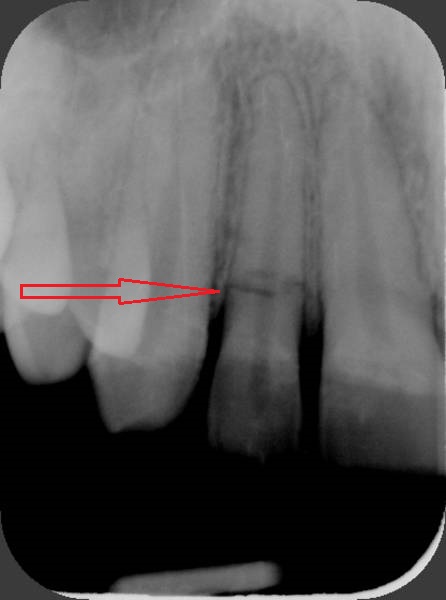

Daimi dişlərin travmatik zədələnmələri uşaq və yeniyetməlik dövründə olan şəxslərdə çox tez-tez rast gəlinir. Tac qırılmaları və lüksasiya travmalar içərisində ən çox rast gəlinənlərdir. Ancaq müxtəlif kliniki hallarda digər zədələnmə formaları da aşkar edilə bilir.

Doğru diaqnostika, müalicə planlaması və sonrakı dönəmdə izləmə uğurlu müalicəyə aparan ən başlıca faktorlardır. Diş travmaları və yaralanmaları tək diş bölgəsini əhatə edən məhdud, eyni zamanda çoxsaylı diş bölgəsini və çənənin alveol darağını əhatə edəcək qədər yayılmış formada rast gəlinə bilir. Çoxsaylı diş zədələnmələrində çox zaman fərqli dişlərdə fərqli növ zədələnmə şəkili aşkar edilə bilir ki, bu da hər bir dişə individual yanaşma və müalicə metodu tələb edir.

Bu tip zədələnmələrin bu sahədə təcrübəsi olan yüksək ixtisaslı həkim tərəfindən həyata keçirilməsi olduqca önəmlidir. Əks təqdirdə yalnış müalicə dişlərin erkən itirilməsinə səbəb ola bilir. Doğru yanaşma ilə isə ciddi zədələnmələrdən sonra belə zədələnmiş dişləri bəzən müəyyən bir müddətə bəzən isə həmişəlik bərpa etmək mümkün olur.